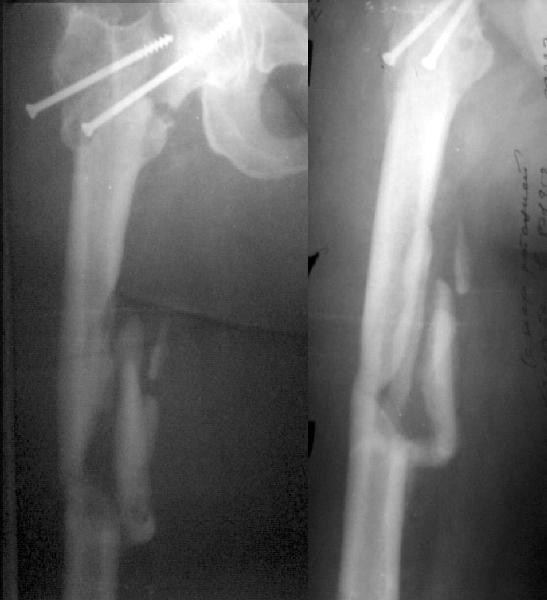

Примерно год назад женщина 44 лет оперирована по поводу перелома шейки и диафиза бедра через 2 нед. после автоаварии. Сделали закрытый остеосинтез бедра стержнем и попытались синтезировать шейку мимо гвоздя.

Пролучилось плохо (снимок N1, через 1 мес. после операции), отчасти благодаря тому, что окружность бедра в верхней трети у нее больше 80 см. Гвоздь на днях удален через старые разрезы. Шейка, понятное дело, не срослась, а диафиз - только на ограниченном участке (снимок N2). Встает вопрос - что делать дальше? Думаем про вальгизирующую остеотомию с фиксацией клинковой пластинкой. Может быть, с ретроградным штифтованием бедра (хотя места между переломом и нижним концом пластинки маловато). Эндопротез с длинной ножкой не доступен. Ожирение - прежнее. Заранее спасибо.